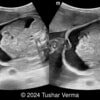

A 33-year-old nullipara with non-contributory medical history presented at 20 weeks, 6 days based on an early scan. Ultrasound revealed the following findings. There were no other apparent abnormalities. What is the most probable diagnosis?